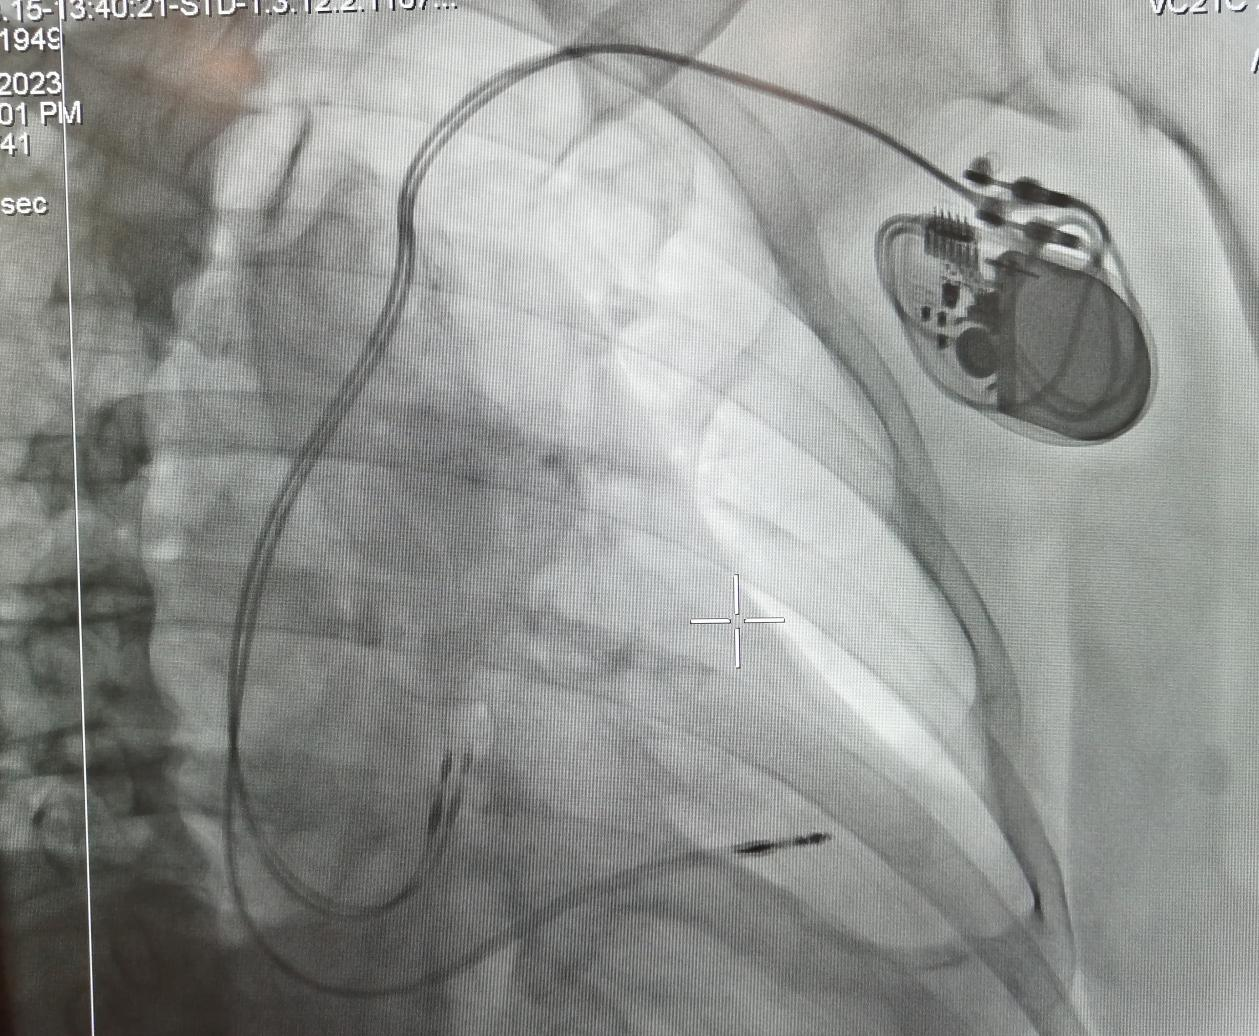

經(jīng)李慧新主任及科室團(tuán)隊(duì)的會(huì)診,予以植入永久性起搏器,同時(shí),李主任將患者的基本病情同白中樂教授進(jìn)行了匯報(bào),術(shù)前白教授詳細(xì)詢問患者的情況,為其制定了更精準(zhǔn)的治療方案,決定實(shí)施永久性起搏器(雙腔)植入術(shù)。8月15日中午,白教授帶領(lǐng)心血管內(nèi)科介入團(tuán)隊(duì)成功為患者實(shí)施了“永久性起搏器(雙腔)植入術(shù)”。術(shù)后患者病情平穩(wěn),無頭暈不適。

起搏器植入后影像圖